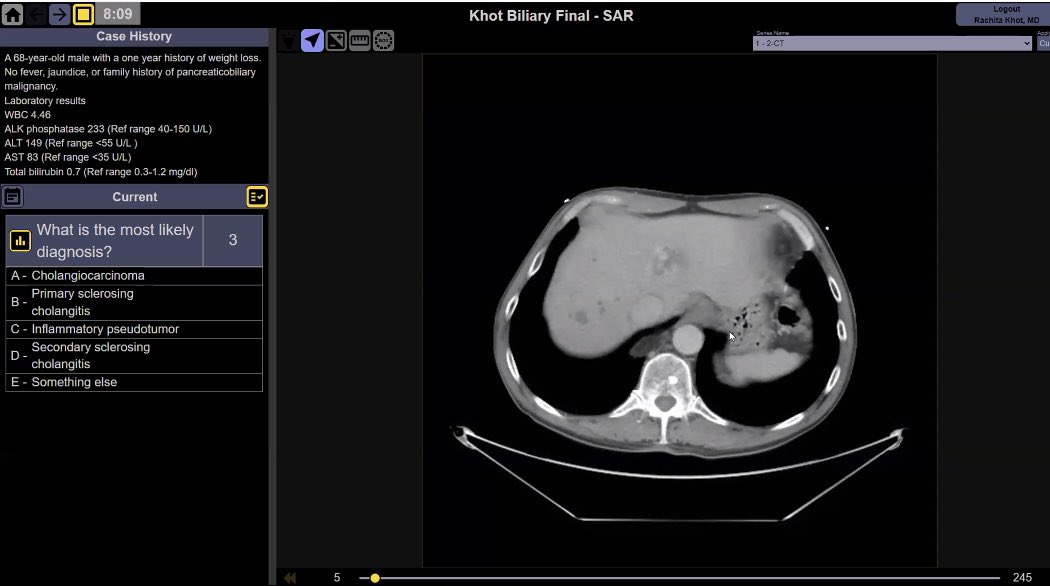

Register ASAP. A hands on experience on four high yield cases with a detailed discussion. Free access. #radiology #radres #radiologist Society of Abdominal Radiology | SAR SAR DFP Benign Biliary Pathology Malak Itani matt_m0rgan @SudhakarKV_MD Mark Anderson, MD

Great Webinar SAR DFP Benign Biliary Pathology Well done team. Excellent cases very well presented. Mark Anderson, MD Sudhakar Venkatesh MD (ಸುಧಾಕರ್ ವೆಂಕಟೆೇಶ್) Hina Arif Rachita Khot matt_m0rgan Society of Abdominal Radiology | SAR Malak Itani Jena Depetris, MD RadPix William Weadock, MD If you missed watch recording at SAR webpage soon. FREE!